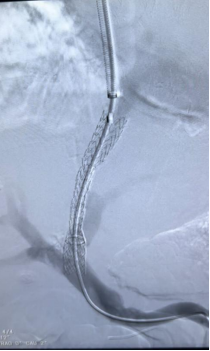

肝硬化食管、胃底静脉曲张破裂出血TIPS介入治疗

肝硬化门脉高压的tips治疗